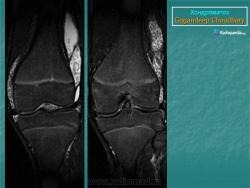

Хондроматоз внутрисуставной (синовиальный).

Хондроматоз

Хондроматоз внутрисуставной (синовиальный)